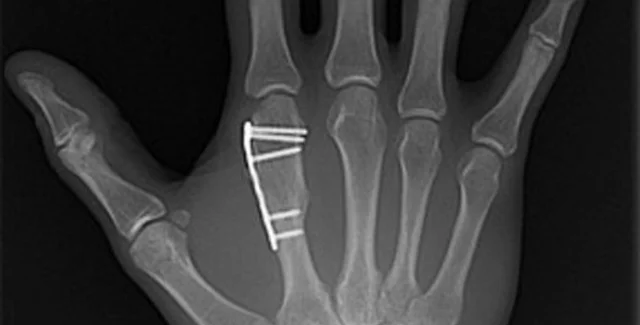

Перед тем, как изготавливать искусственную кость медикам будет нужно сделать рентгеновский снимок и томограмму поврежденного участка, чтобы в дальнейшем система изготовления костной ткани могла в точности воспроизвести размеры и форму поврежденной кости. Сообщается, что технология производства способна производить кости довольно замысловатой формы, например, челюсти или фрагменты черепа. Минимальная толщина искусственной кости составляет 1 мм, что более чем достаточно для подавляющего большинства костей в организме.